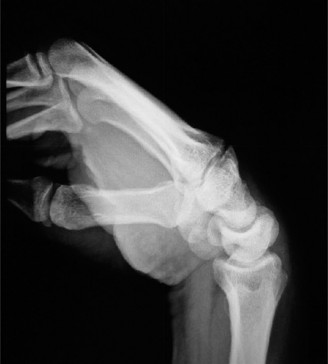

Radiographic evaluation requires specific, non-standard views. A standard PA and lateral of the wrist will often obscure the pisiform due to bony overlap. Therefore, a 30-degree supinated lateral view or a carpal tunnel view is essential to profile the pisiform and evaluate the pisotriquetral joint space. In cases of delayed union or subtle comminution, a fine-cut non-contrast Computed Tomography (CT) scan provides invaluable three-dimensional mapping. For the elderly patient presenting with progressive, non-traumatic base of thumb pain, standard radiographs must include a Robert's view (a true AP of the first CMC joint) and stress views to evaluate the degree of radial subluxation. The image above clearly demonstrates advanced 1st CMC arthritis, characterized by complete loss of joint space, subchondral sclerosis, and osteophyte formation, confirming the diagnosis.